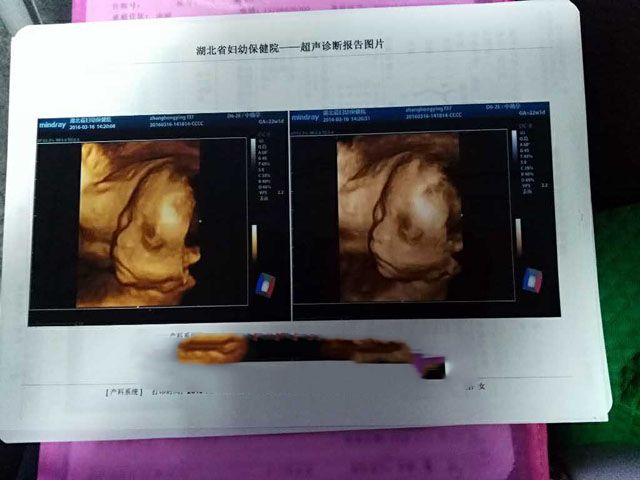

要不要看看产检记录!

2016年7月4日,孕37周,男宝宝顺利降临。